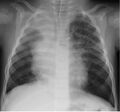

English: Figure. . Chest radiograph of the index patient, a 16-month-old boy in Finland with human bocavirus 1 pneumonia, on day 2 of hospitalization. Bilateral pulmonary infiltrations and atelectasis of the upper right lobe can be seen. |

| Source | Emerging Infectious Diseases, Volume 19, Number 8—August 2013, http://wwwnc.cdc.gov/eid/article/19/8/13-0074-f1.htm |

| Author | Alma Jula, Matti Waris, Kalle Kantola, Ville Peltola, Maria Söderlund-Venermo, Klaus Hedman, and Olli Ruuskanen |